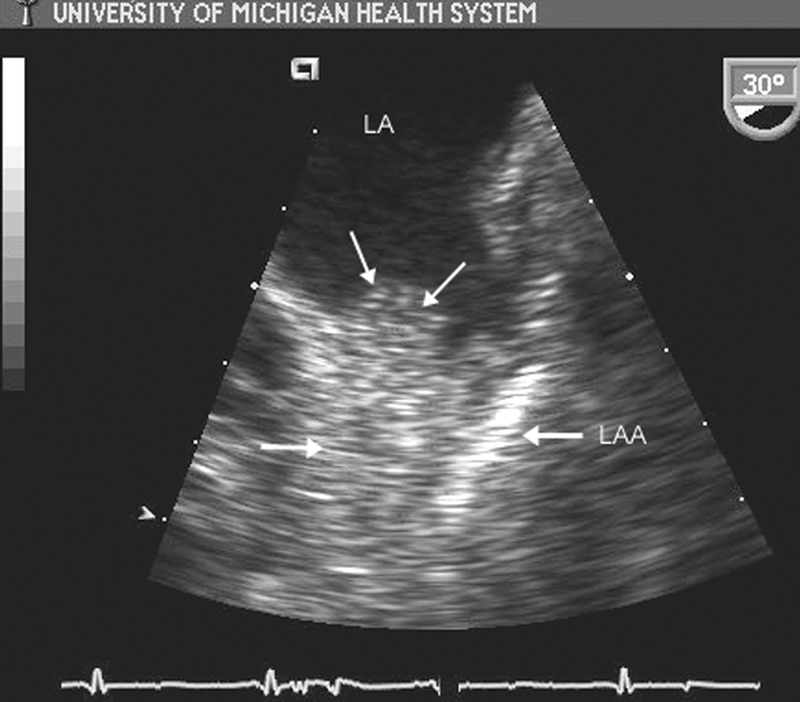

فحوصات تشخيصية لبعض امراض القلب والشرايين التاجية